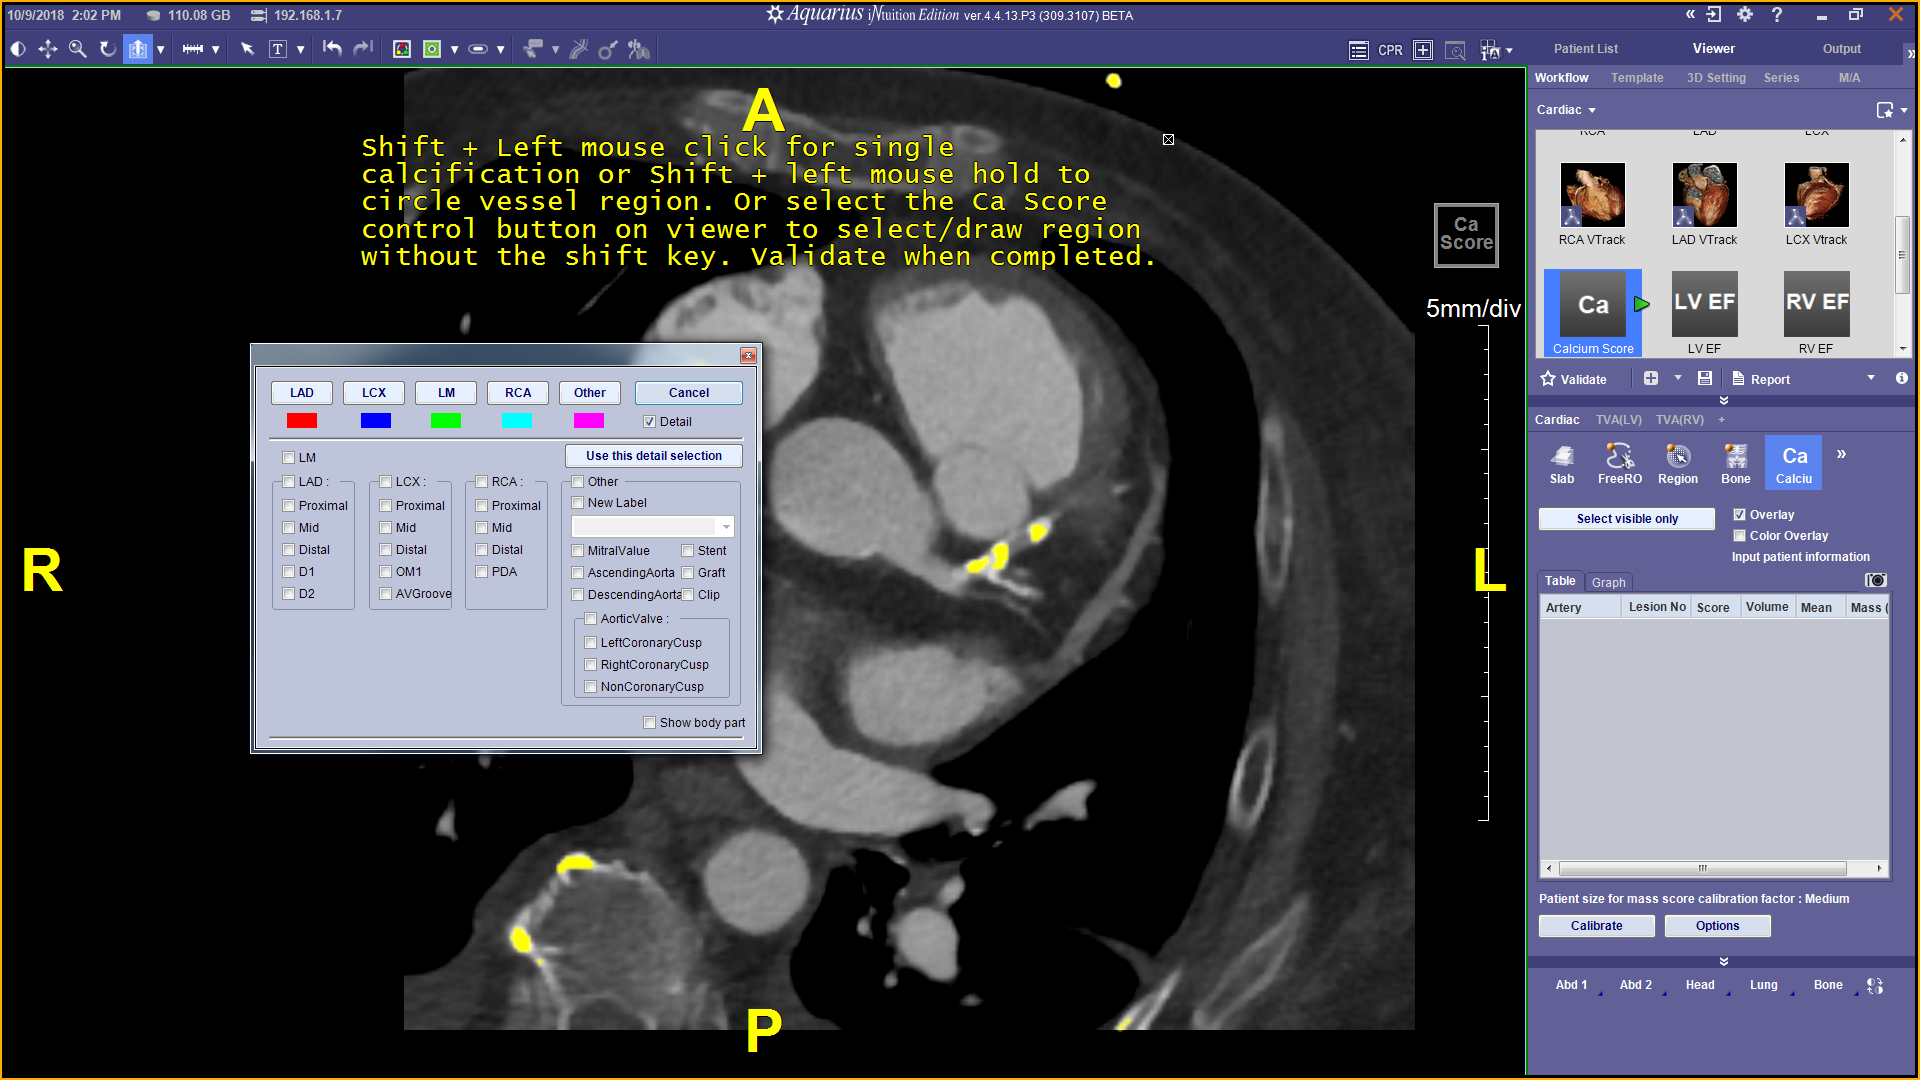

From www.terarecon.com

CT Cardiac Advanced Visualization Package Terarecon Ct Cardiac Scoring Promotion Web in asymptomatic patients without established atherosclerotic cardiovascular disease (ascvd), the. Web how much does a cardiac ct calcium scoring cost? Web current guidelines recommend measuring coronary artery calcification (cac) scoring for stratification of. Purchase a cardiac ct calcium scoring today on mdsave. Web the ct scans your heart and the measurement of calcification produces a score that shows the. Ct Cardiac Scoring Promotion.